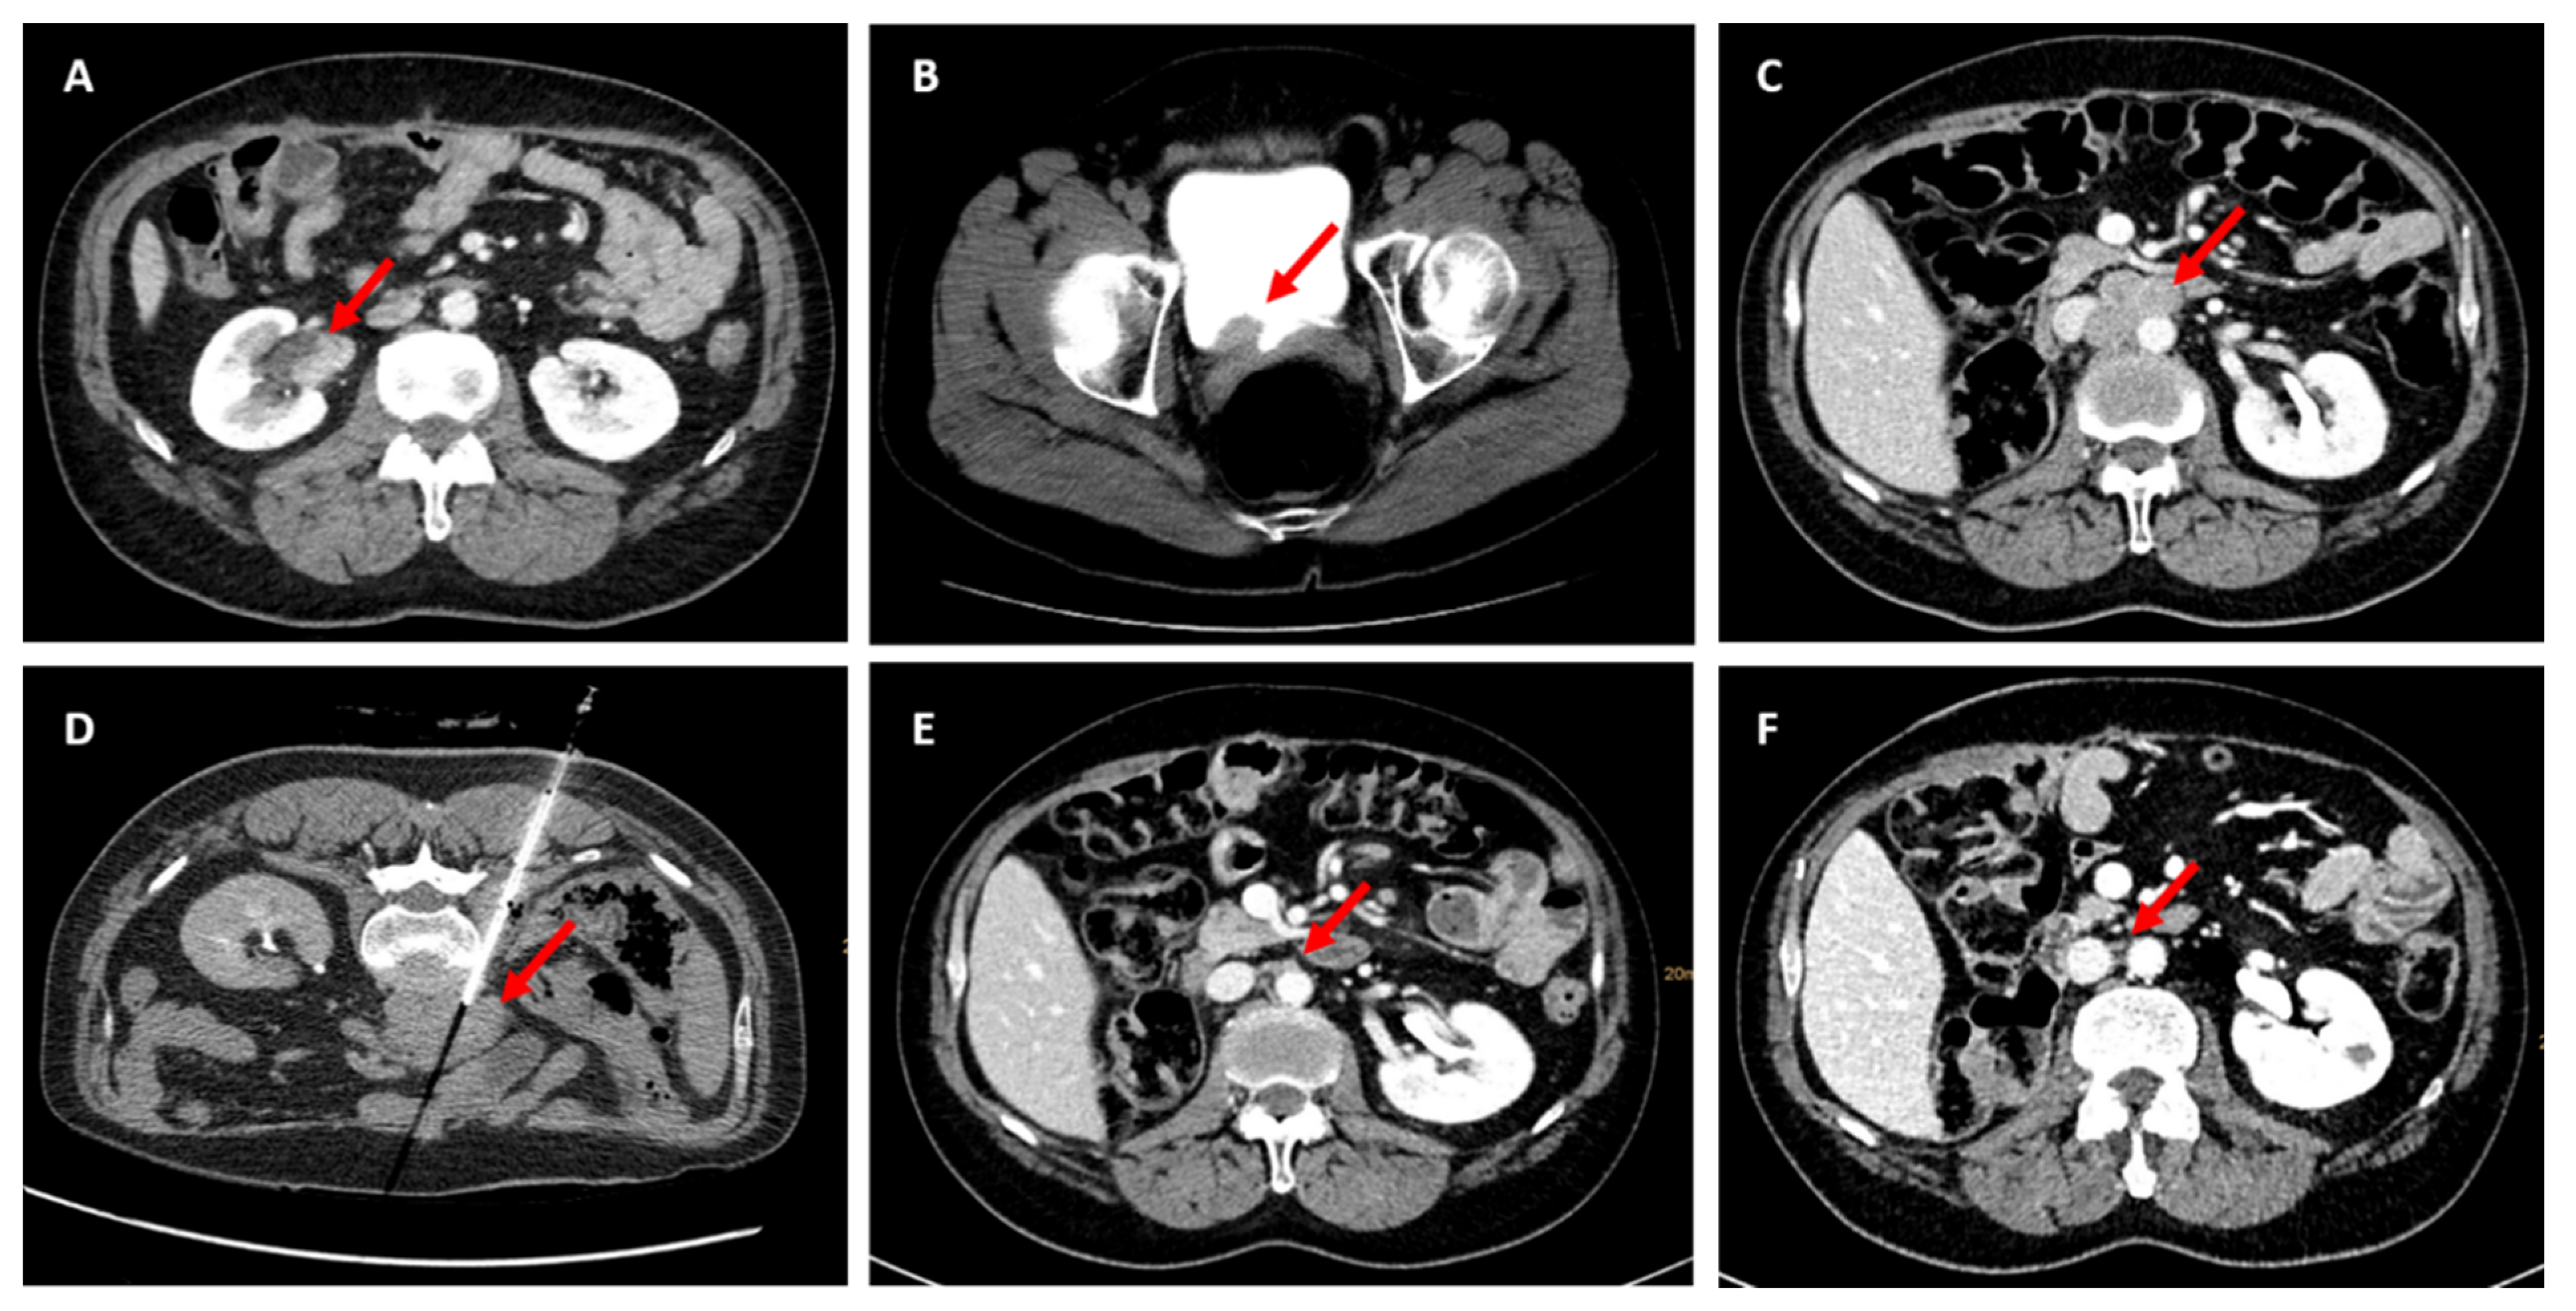

2. Case Presentation